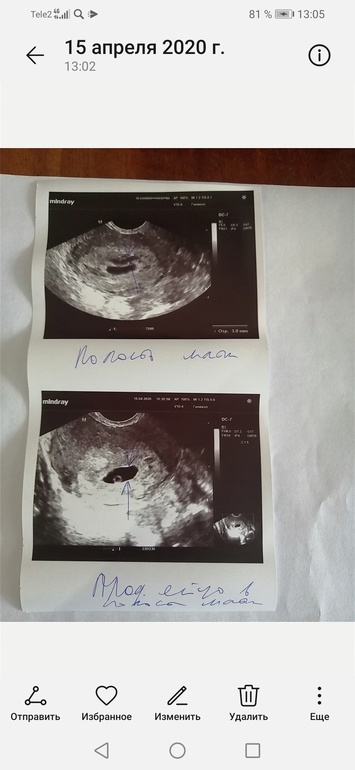

Здравствуйте подскажите пожалуйста была на узи гинеколог сказала желточный мешочек есть и плодное яйцо в матке, а эмбриончика ещё не видно сказала придти через 10 дней, в остальном все хорошо ставит 5-6 недель, стоит ли переживать? Анализы уже начала сдавать, сказала что на учет поставит 28 числа Жидкости в позадиматочном пространстве не обнаружили, как мне говорил узист сначала, но мой врач сказала что узист это не гинеколог и ей виднее, все равно волнуюсь, принимаю витамины вемибион Заранее благодарю вас за ответ🌹

Желточный мешок 4 мм, плодное яйцо внутр размер 16*12*10мм,эхоструктура плодного яйца и желточного мешка нормальная, это было в 4,5-5 недель

Плодное яйцо- 9мм

Желточный мешок- 2,1

Эмбрион тоже не визуализировался